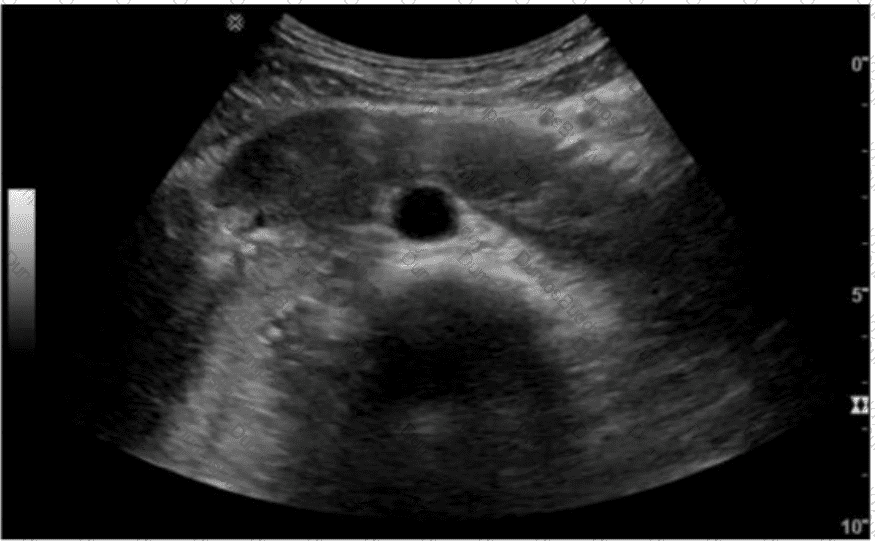

Which condition is most likely the cause of claudication experienced two weeks after this image was obtained?